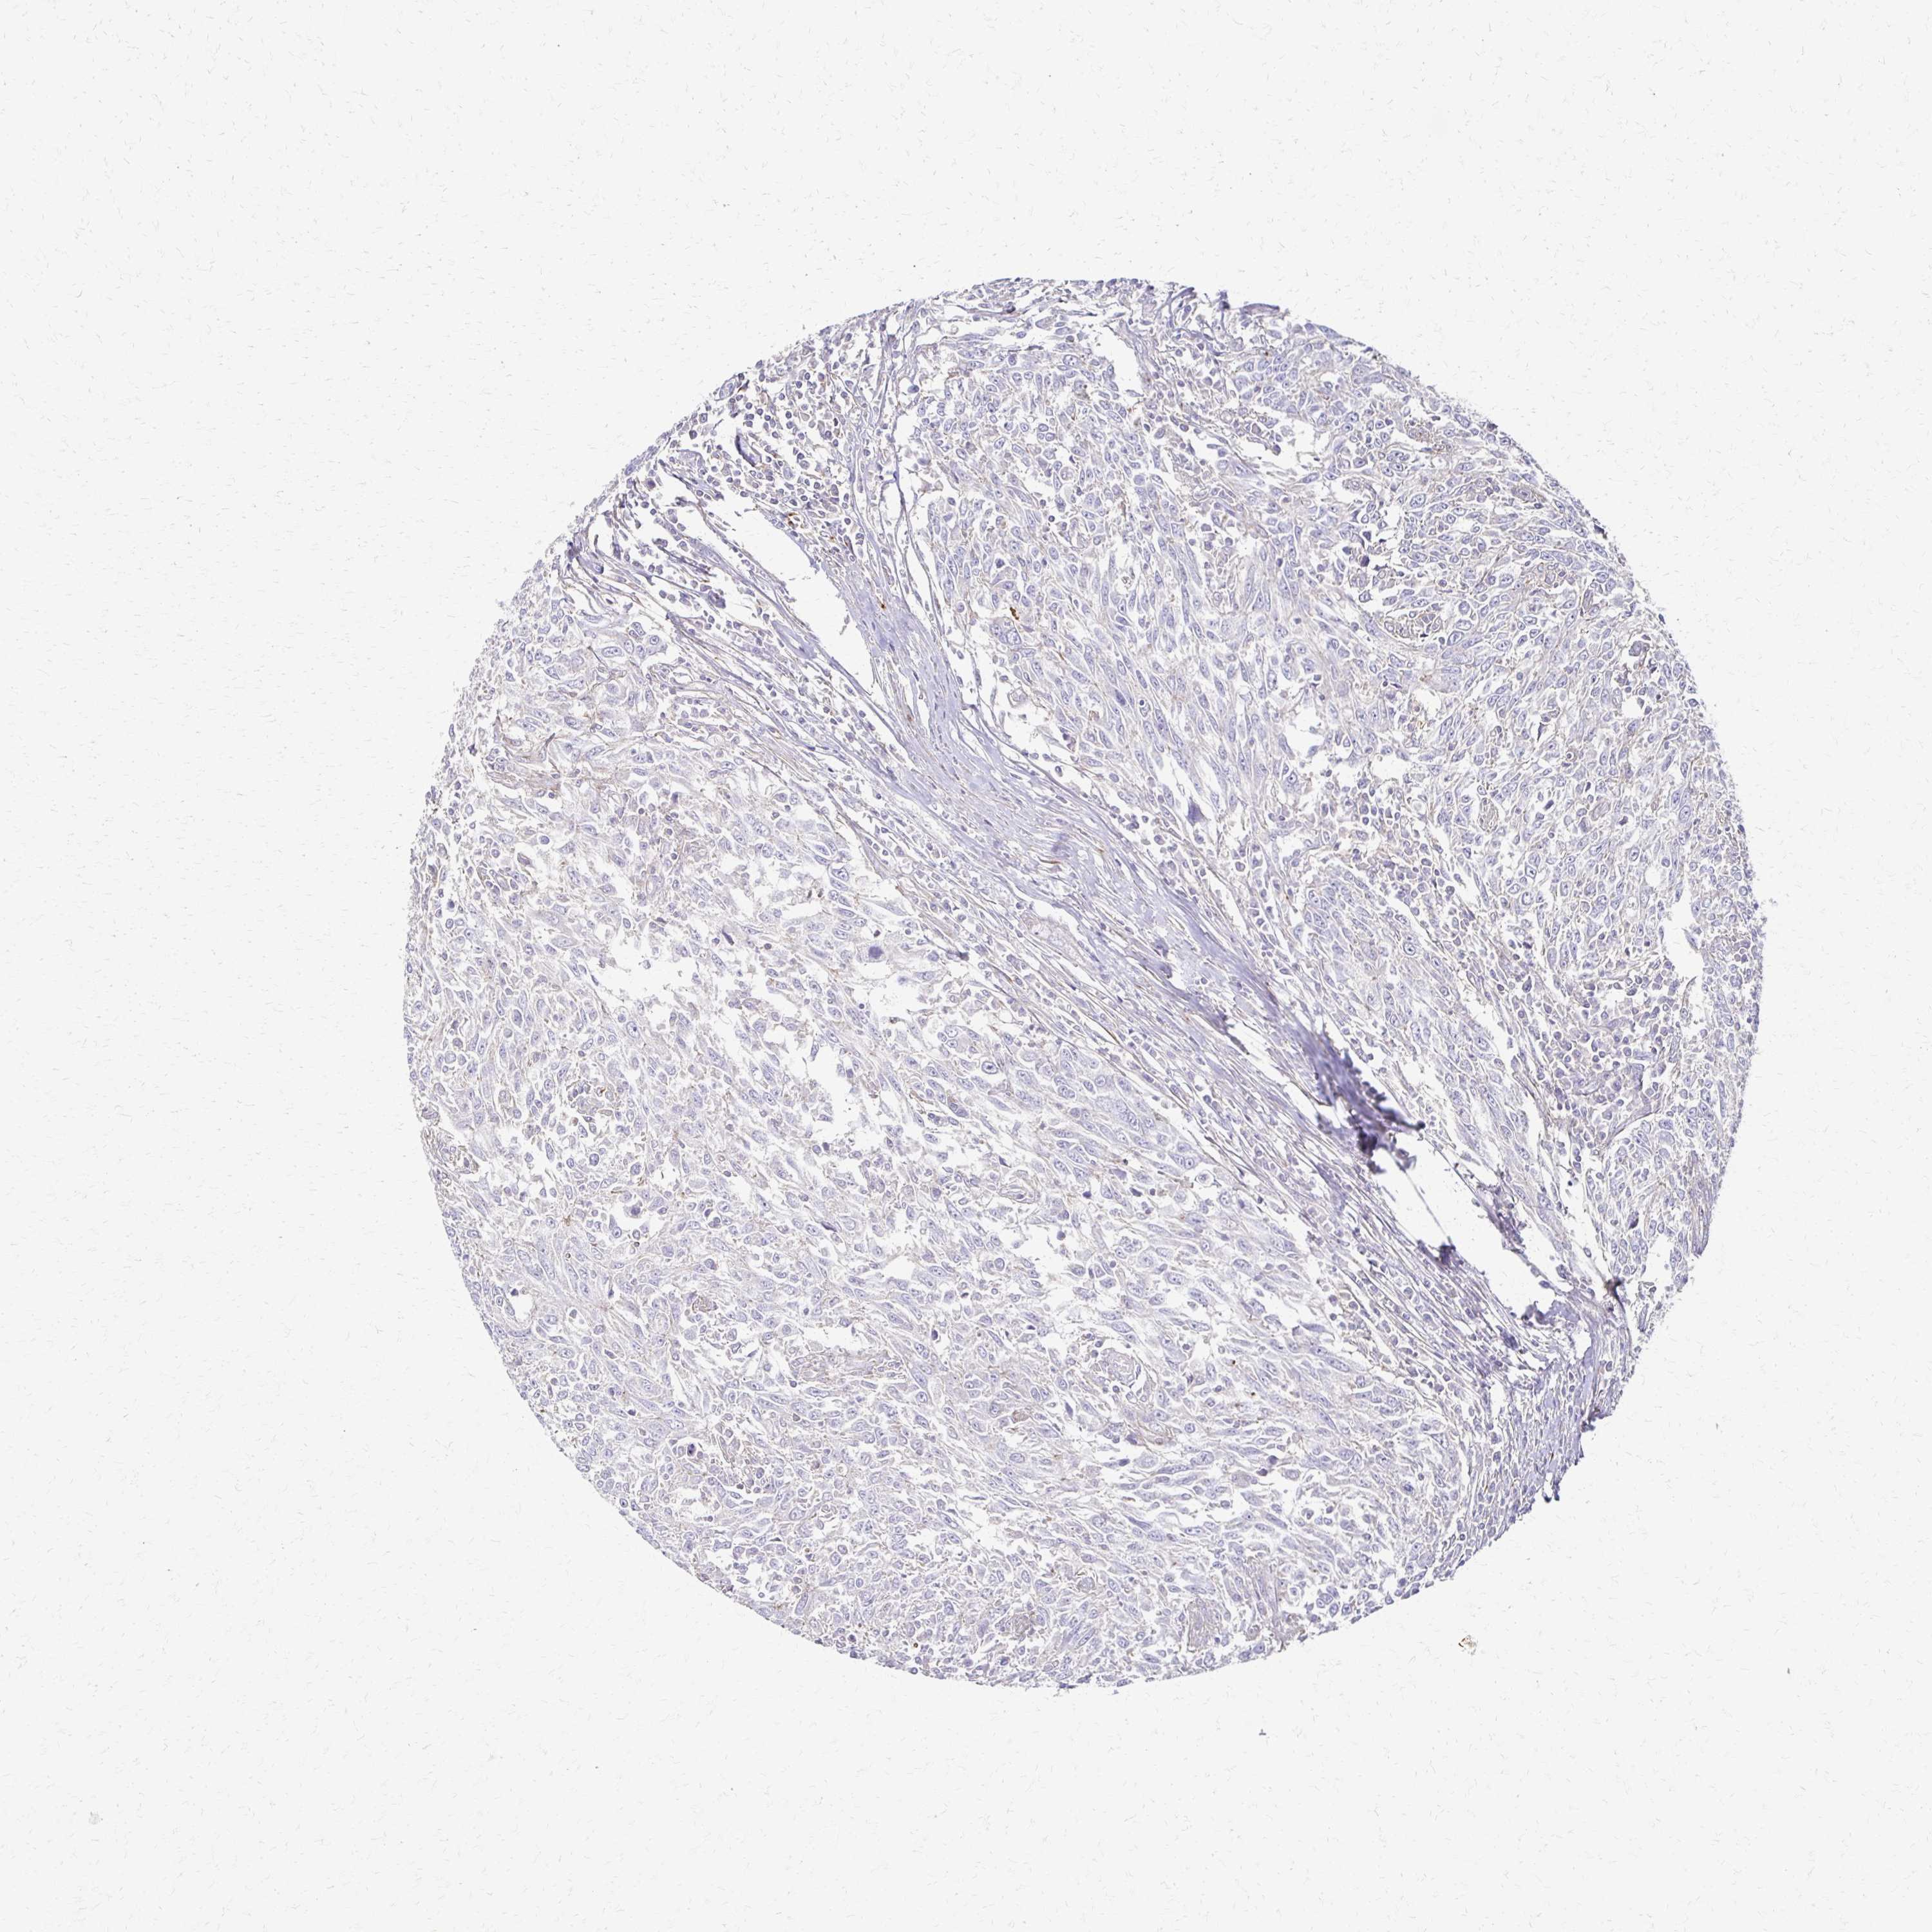

BRCA TCGA BRCA VALIDATION PROTEIN EXPRESSION

ANTIBODIES

AND

VALIDATION